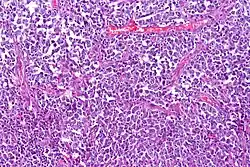

Histological sample of diffuse large B-cell lymphoma (DLBCL)

Lymphoma cancer types have varying probabilities of metastasizing to the CNS, resulting in secondary CNS lymphoma (SCNSL), which may appear simultaneously as systemic lymphoma, or as remission after systemic lymphoma is treated. Synchronous, or de novo disease is diagnosed in approximately 40% of patients and relapse in 60%.[8] Overall, CNS involvement is observed in 2 to 27% of patients with aggressive systemic non-Hodgkin’s lymphoma.[5] 5% of patients with diffuse large B cell lymphoma, the most common type of non-Hodgkin lymphoma, result in SCNSL but account for most SCNSL cases.[3]